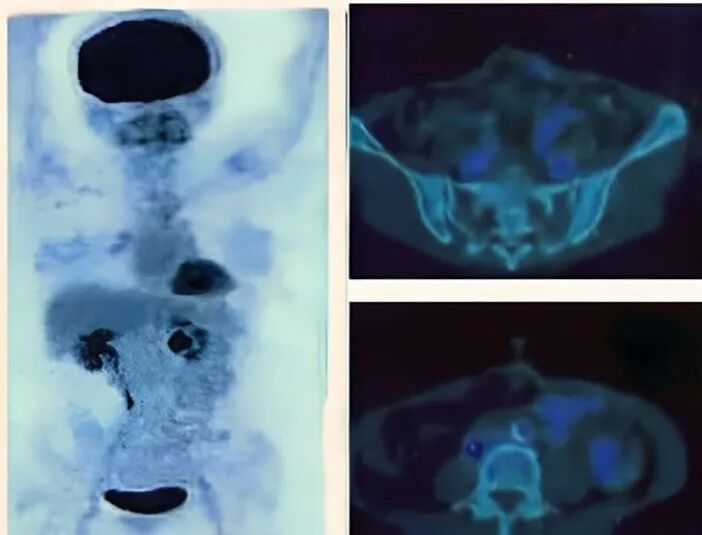

患者因横结肠肿瘤相关部分性肠梗阻和血性腹泻就诊,2018年12月接受了横结肠切除术,病理结果显示为III期横结肠腺癌,淋巴结受累阳性。术后两个月,CEA(癌胚抗原)水平为1.3ng/mL。术后6个月,PET-CT扫描显示间膜淋巴结葡萄糖摄取呈阳性,怀疑肿瘤复发。

临床人员进行为期两周的NK细胞扩增和激活后,将其输回患者体内。患者接受了2个周期的NK细胞治疗,第二次治疗间隔3个月。术后3年随访的PET-CT扫描显示,未发现新的葡萄糖摄取,患者对治疗耐受性良好,未报告任何免疫相关不良反应。截至2022年12月,患者未出现局部区域复发的迹象,日常生活恢复正常。

图片图:接受NK细胞疗法后,免疫相关的不良反应消失